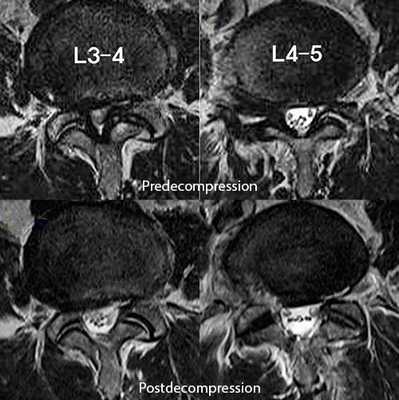

При определении показаний к операции в случае установления диагноза стеноза позвоночного канала следует учитывать распространенность процесса. При операциях на одном или двух уровнях позвонков и односторонних симптомах компрессии корешков может быть использована интерламинотомия или гемиламинэктомия.

При двусторонних симптомах компрессии нервно-сосудистых образований позвоночного канала и на нескольких уровнях, может быть выполнена двусторонняя гемиламинэктомия с сохранением остистых отростков и межостистой связки, иссекаются гипертрофированная желтая связка, остеофиты. Целесообразно при стенозе позвоночного канала параллельное проведение фораминотомии. В отдельных случаях стеноза позвоночного канала бывает необходимо использование стабилизирующих позвоночник металлоконструкций.

На МРТ поясничного отдела позвоночника показан стеноз позвоночного канала и состояние после операции эндоскопической декомпрессии на уровнях L3-L4 и L4-L5.

Иногда при стенозе позвоночного канала бывает целесообразно разделить операцию на два этапа. На первом этапе выполняется декомпрессия наиболее страдающих корешков спинного мозга, проводится курс интенсивной вазоактивной и нейростимулирующей терапии. И, если не достигнуто улучшение и облегчение состояния больного, можно предложить второй этап операции — более широкую декомпрессию (двустороннюю гемиламинэктомию) и создание дополнительных резервных пространств при стенозе позвоночного канала.